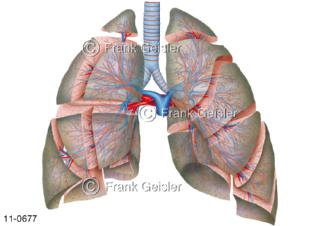

11-0677 Lungensegmente der Lunge mit Luftröhre Trachea Bronchien und Blutgefäße